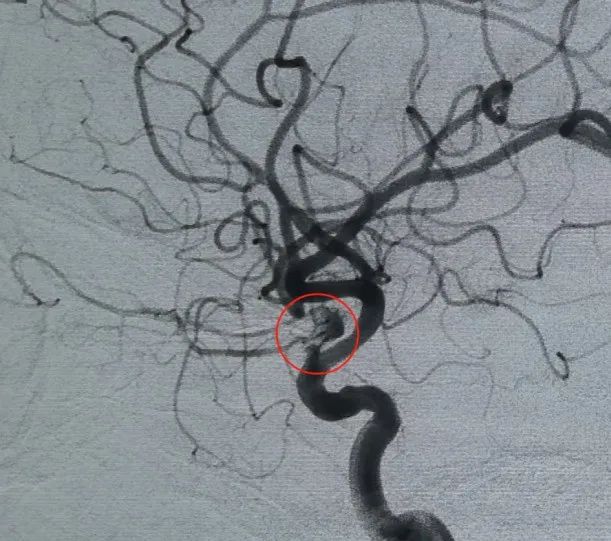

Diagnóstico: Aneurisma de la arteria carótida interna izquierda del segmento C6 de la arteria oftálmica

El acceso vascular se estableció mediante punción de la arteria femoral y un Perdenser®La bobina 3D de 6mm × 20 cm se desplegó por primera vez para formar una canasta, logrando una aposición estable de la pared y proporcionando un soporte intrasaccular seguro. Esto fue seguido por la inserción de un Perdenser®Bobina 3D de 6mm × 15 cm para interrumpir el flujo sanguíneo dentro del saco hija lobulado.

Un Perfiller®3mm × 6 cm bobina expansible y un Perfiller®A continuación se colocaron bobinas expansibles de 3mm x 2 cm para completar la oclusión del cuello. Posteriormente, un Nuva®Se administró un desván de flujo (TJED-D-5.0-16) y se desplegó a través del cuello del aneurisma. La angiografía de seguimiento en las vistas anteroposterior y lateral confirmó una excelente cobertura, buena aposición de la pared y clara radiopacidad, con marcado estancamiento del contraste.